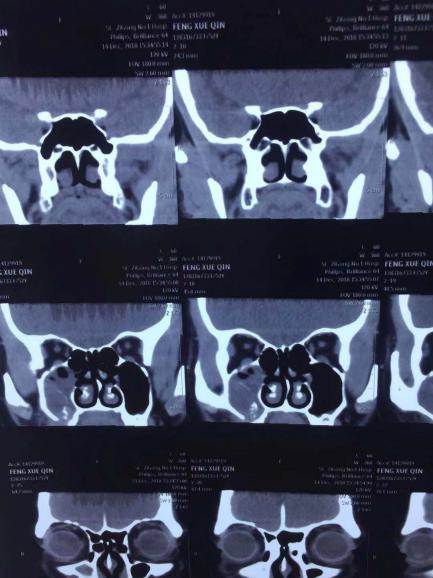

经门诊主任问诊,以及CT检查发现:冯女士右侧上颌窦存在钙化斑、积液,外下壁显示异物、局部软组织隆起。结合其病史,初步推断病因为种植牙异物(种植体)进入上颌窦较深,形成炎性死骨,又因没有对症治疗,导致炎症扩散后引发鼻窦炎。